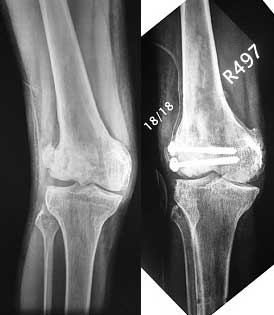

Post-op - limb is well aligned, rom 0-30, but I am not pushing that right now, for the next two or three weeks.

Further plan - hope that the screws hold the fragment appropriately till union, but if the stability on table is anything to judge by, that should not be a problem.

Quadricepsplasty after a year or so, to restore flexion.

Very probably you have done maximum of what could be done - accurate and low invasive indirect reduction, auto grafting, rigid fixation.